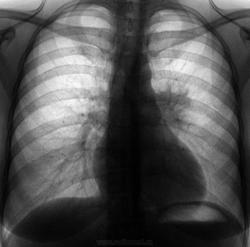

Такая флюшка, 30 лет,  архива нет, про жалобы не заявила (обычно лаборанты такое фиксируют), стало быть профилактическая. Что делать?

Сделали боковуху + пациентка под "пытками" рассказала, что немного ранее было недомагание, кашель, t. Сейчас состояние сносное. Все и прояснилось, S6.  А по прямому можно придумать бог весть что.

Наверное туберкулёз( С6).

сколько угодно и о чём угодно в том случае, если мы будем знать, что увидим контроль.  Изложу  все-таки свою точку зрения ради пациентки. У  больной имеет место туберкулез внутригрудных лимфатических узлов левой бронхопульмональной группы, бронхолёгочное поражение S6. Брохоскопия в ПТД . Пробное лечение антибиотками не оправдано.

Не стал заморачиваться в отношении корня, посчитал инфильтрация в S6 наложилась на него. Написал пневмонию. Не знаю, где будет лечится. Если у нас и будет на контроле - обязательно выставлю.